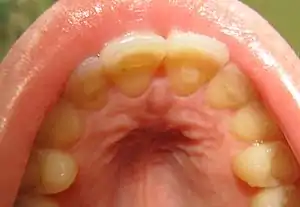

| Loss of enamel (acid erosion) from the inside of the upper front teeth as a result of bulimia | |

- Perimolysis, or severe dental erosion of tooth enamel[21]

People with bulimia are more likely than people without bulimia to have an affective disorder, such as depression or general anxiety disorder. One study found 70% had depression at some time in their lives (as opposed to 26% for adult females in the general population), rising to 88% for all affective disorders combined.[29] Another study by the Royal Children's Hospital in Melbourne on a cohort of 2,000 adolescents similarly found that those meeting at least two of the DSM-IV criteria for bulimia nervosa or anorexia nervosa had a sixfold increase in risk of anxiety and a doubled risk for substance dependency.[30] Some with anorexia nervosa exhibit episodes of bulimic tendencies through purging (either through self-induced vomiting or laxatives) as a way to quickly remove food in their system.[31] There may be an increased risk for diabetes mellitus type 2.[32] Bulimia also has negative effects on a person's teeth due to the acid passed through the mouth from frequent vomiting causing acid erosion, mainly on the posterior dental surface.